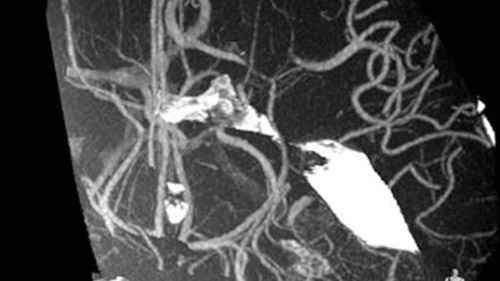

FlexVision XL visualizes brain vasculature at the capillary level in both 2D and 3D and allows flexible switching of videos sources, screen layout, and image size from tableside.

Stroke treatment is growing, fueled by availability of new devices. Philips Stroke Suite contains: XperCT, VasoCT, MR/CT Roadmap, XperGuide, FlexVision XL, and Roadmap Pro.